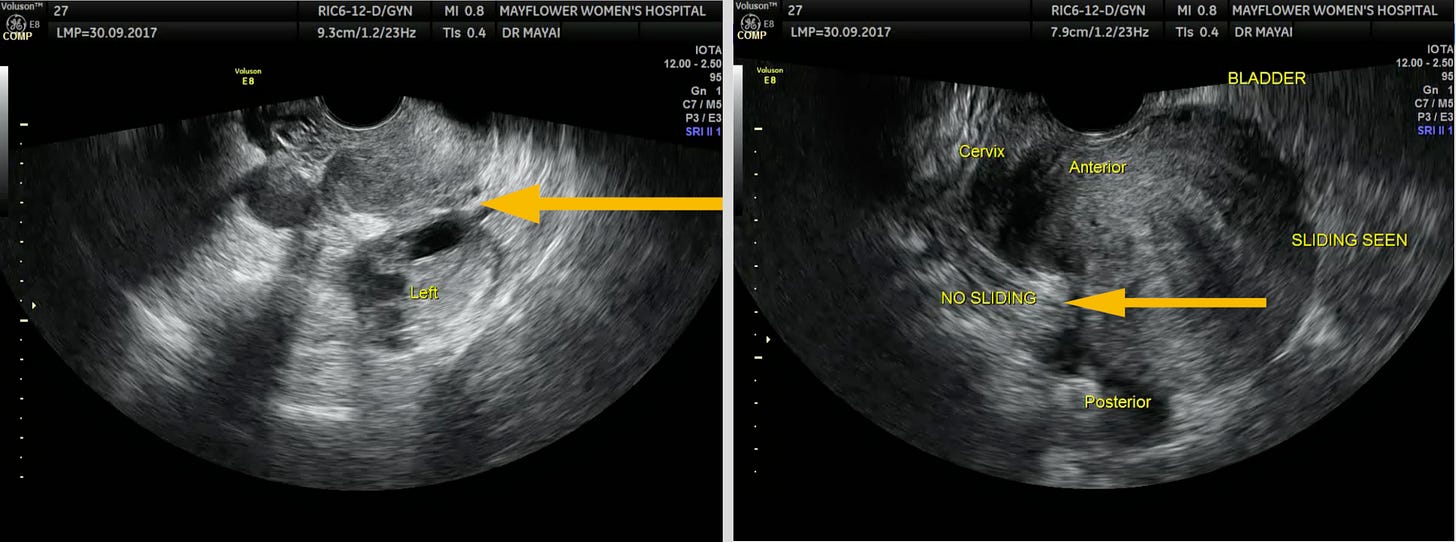

Being able to move the TVS probe to observe sliding between the organs, might be the single most distinctive feature of the technology aiding in an early detection of adhesions inside the pelvis.

But USG can only go so far in determining the true extent of the disease. While it denotes the presence of endometriosis, it doesn’t help us accurately map the most damning feature of the disease. It’s infiltration.